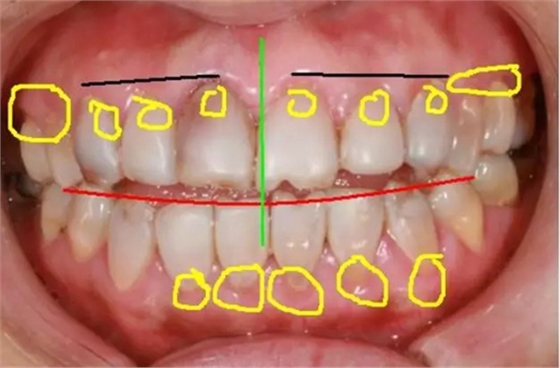

如下面圖一照片,我們?cè)诨颊咝枰淖兊牡胤椒謩e做了標(biāo)記,并進(jìn)行先期的設(shè)計(jì)。

(圖一)

1,黑線牙齦的高度:

患者左側(cè)牙齦高度較正常,右側(cè)13的牙齦明顯低于12,右側(cè)牙齦至少要與左側(cè)接近。

2,紅線切緣:

由于患者開頜較重,縱面曲線已經(jīng)改變,所以在美學(xué)修復(fù)的同時(shí),應(yīng)注意牙齒生理上意義。

3,綠線正中線:

正中線是起到一個(gè)均衡的意義,除上下頜盡可能對(duì)齊外,同時(shí)要保證必須與面中線一致。

4,黃線處牙齦:

患者的牙齦(牙周)已經(jīng)明顯紅腫,必須要在牙周穩(wěn)定后才能進(jìn)行修復(fù)。如果是原修復(fù)體的原因,建議先拆除,去除對(duì)牙齦的刺激。如果是患者自身原因,建議治療后觀察,修復(fù)治療待定。